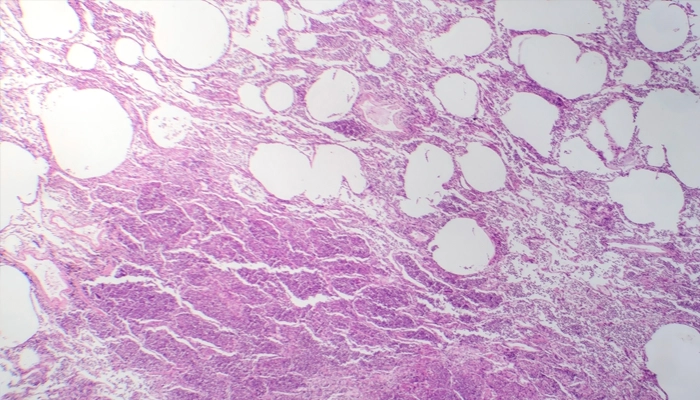

Hình ảnh vi thể của viêm phổi kẽ, cho thấy tình trạng viêm và xơ hóa ở mô kẽ của phổi.

Viêm phổi kẽ là tình trạng viêm và tổn thương mô kẽ của phổi – tức là phần mô liên kết nằm giữa các túi khí (phế nang) và mạch máu phổi.

Khi bị viêm: Mô kẽ dày lên, xơ cứng, làm giảm khoảng cách và diện tích trao đổi khí. Phổi trở nên kém đàn hồi, từ đó gây khó thở kéo dài và thiếu oxy máu.